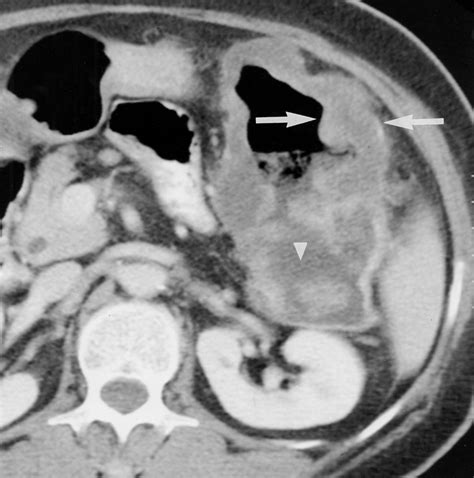

- Ischemia: If the blood supply to a portion of the intestine is compromised (bowel ischemia), the tissue may swell and become thick.

- bowel wall thickening on ct

- bowel wall thickening radiology